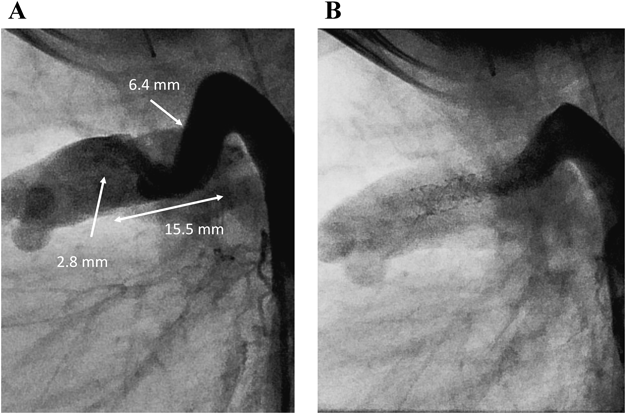

症例2は,DORV/PA, 18トリソミーで,開心術のリスクが高く生後11か月までプロスタグランジン製剤の持続投与を継続されていた.当初は積極的治療を行わない方針だったが,両親より在宅移行の希望を認め,DSを目的に他院から紹介された.生後11か月,体重4.8 kgで左総頸動脈穿刺によるDSを行った.動脈管は屈曲しており,MULTI-LINK 8® 4.0×12.0 mm(Abbott; Chicago, IL)を留置した(Fig. 3).その後の経過は良好で,速やかに在宅移行が可能だった.

Pediatric Cardiology and Cardiac Surgery 36(4): 294-305 (2020)

Fig. 3 Case 2: DS for DORV/PA, 18 trisomy

A) Lateral view of “straight” ductus arteriosus angiography revealed originating from thoracic aorta. B) Angiography after DS. DORV/PA: Double-outlet right ventricle/pulmonary atresia